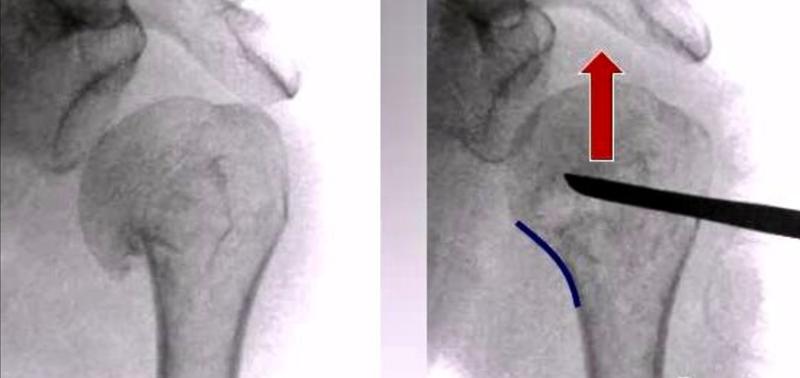

(5)由于胸大肌的牵拉,肱骨干通常都向内移位。

图14 可以先将钢板固定在肱骨头外侧面,而此时骨干可能仍然存在向内移位,在骨折线远端的第一个螺钉孔置入一枚3.5mm皮质骨螺钉将肱骨干向外提拉复位

图15 通过提拉,达到解剖复位